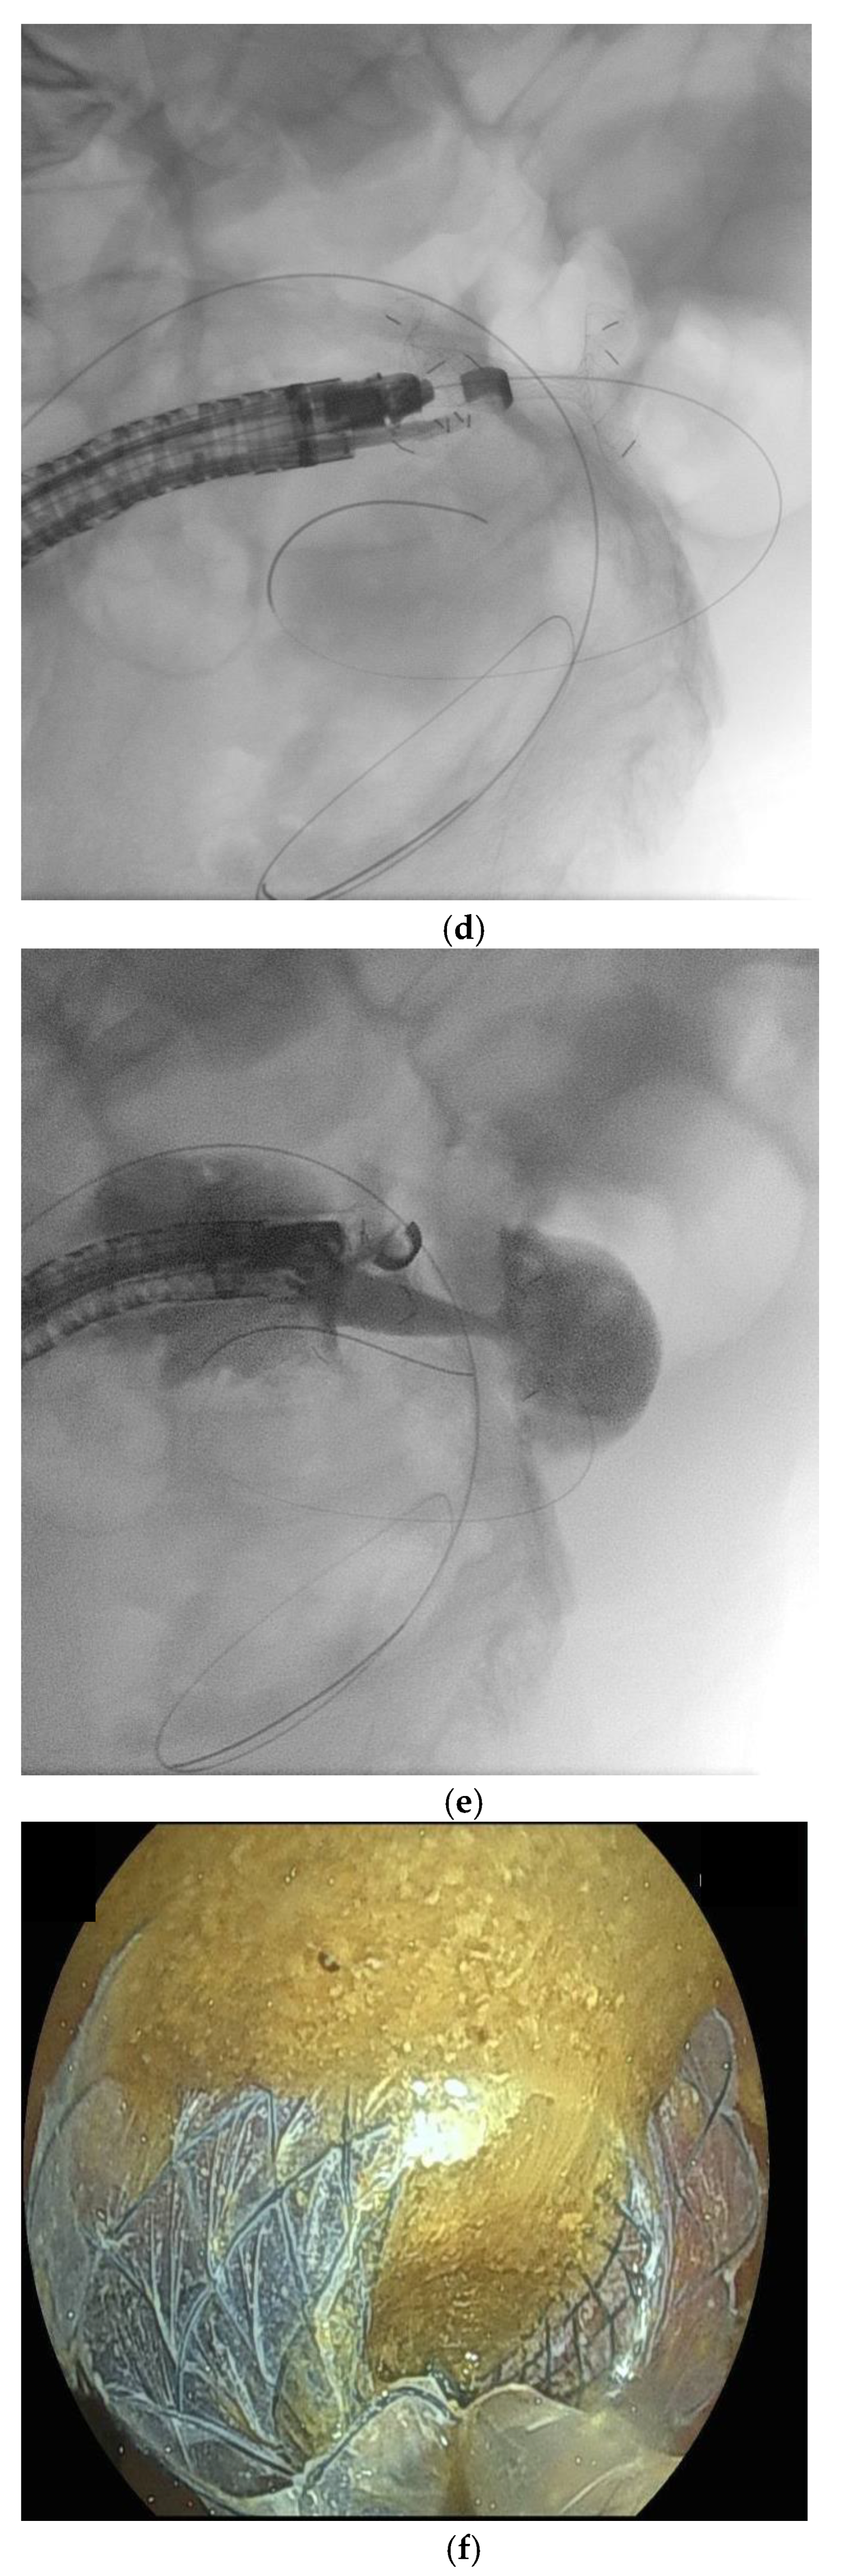

10. Endoscopic Ultrasound-Guided Entero-Colostomy with LAMS

- Neri, B.; Stigliano, S.; Biasutto, D.; Citterio, N.; Lisotti, A.; Fusaroli, P.; Mangiavillano, B.; Donatelli, G.; Tonini, G.; Di Matteo, F.M. Endoscopic ultrasound-guided entero-colostomy with lumen-apposing metal stent as a rescue treatment for malignant intestinal occlusion: A multicenter study. Endoscopy 2025, 57, 77–82. [Google Scholar] [CrossRef]